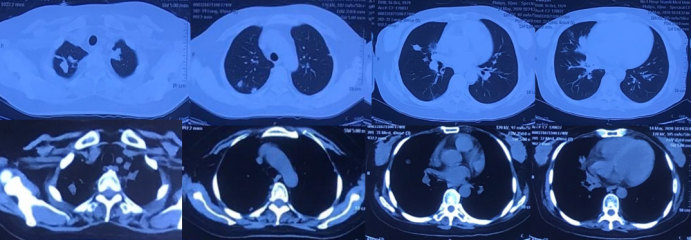

患者半年前因“成人Still病”开始口服激素(醋酸泼尼松片20 mg qd)及环孢素(50 mg bid)治疗,用药期间患者出现咳嗽、咳痰症状,黄白色黏痰,量不多,不易咳出,无胸闷、气短、胸痛、咯血等不适,就诊于北京某医院,完善胸部CT示“双肺多发肿块影及结节影,部分内伴空洞”,该院考虑真菌感染,予口服伏立康唑治疗1周。用药后患者咳嗽、咳痰症状一度缓解。自2020年2月开始,患者咳嗽、咳痰加重,间断出现发热,体温最高可达40℃,伴有畏寒,无寒战、呼吸困难等其他症状,调整激素为早晚各一次(醋酸泼尼松片10 mg/次),但患者体温控制较差,于3月15日(图1)及4月20日(图2)复查胸部CT检查,提示双肺多发肿块影及结节影,部分内伴空洞形成,病灶有增大、增多趋势。为求进一步诊治收入我院。

图1  患者胸部CT(2020-03-15)

图2  患者胸部CT(2020-04-20)

胸部CT(2020-03-17):双肺多发肿块影及结节影,较大者大小约为3.7  cm×2.7 cm,部分内伴空洞。胸部CT(2020-04-20)示:双肺多发肿块影及结节影,较大者大小约为9.68 cm×5.4 cm,部分内伴空洞,与前片对比,病灶明显增大、增多;心包少量积液。

转入我科1周后,复查胸部CT示肺部病灶较前进一步进展(图3)。患者右小腿皮肤破溃范围扩大至4 cm×7 cm,周围红肿约6 cm×10 cm,肉芽组织不新鲜,有少许分泌物(图4)。此时痰、肺泡灌洗液(BALF)培养及mNGS结果回报均为鼻疽诺卡菌序列数44783)、金黄色葡萄球菌(序列数187,对TMP-SMX耐药,对美罗培南、利奈唑胺敏感。根据药敏结果换用美罗培南联合利奈唑胺继续抗感染治疗。右小腿皮肤破溃处请中医科会诊后给予中药化腐清创术、去腐生肌膏外用。

图3  患者转入我科1周后复查胸部CT